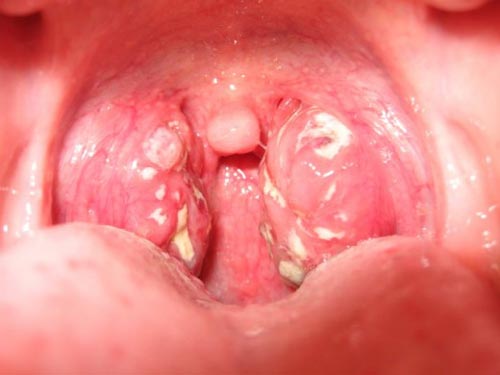

2. Dấu hiệu lậu ở miệng (oral gonorrhea)

Hơn 70% trường hợp không có triệu chứng, nhưng khi có dấu hiệu, thường gặp:

Triệu chứng đặc trưng:

- Đau họng kéo dài, giống viêm họng hạt

- Rát họng, nuốt đau

- Sưng amidan, có mảng trắng hoặc mủ

- Hơi thở hôi

- Sốt nhẹ